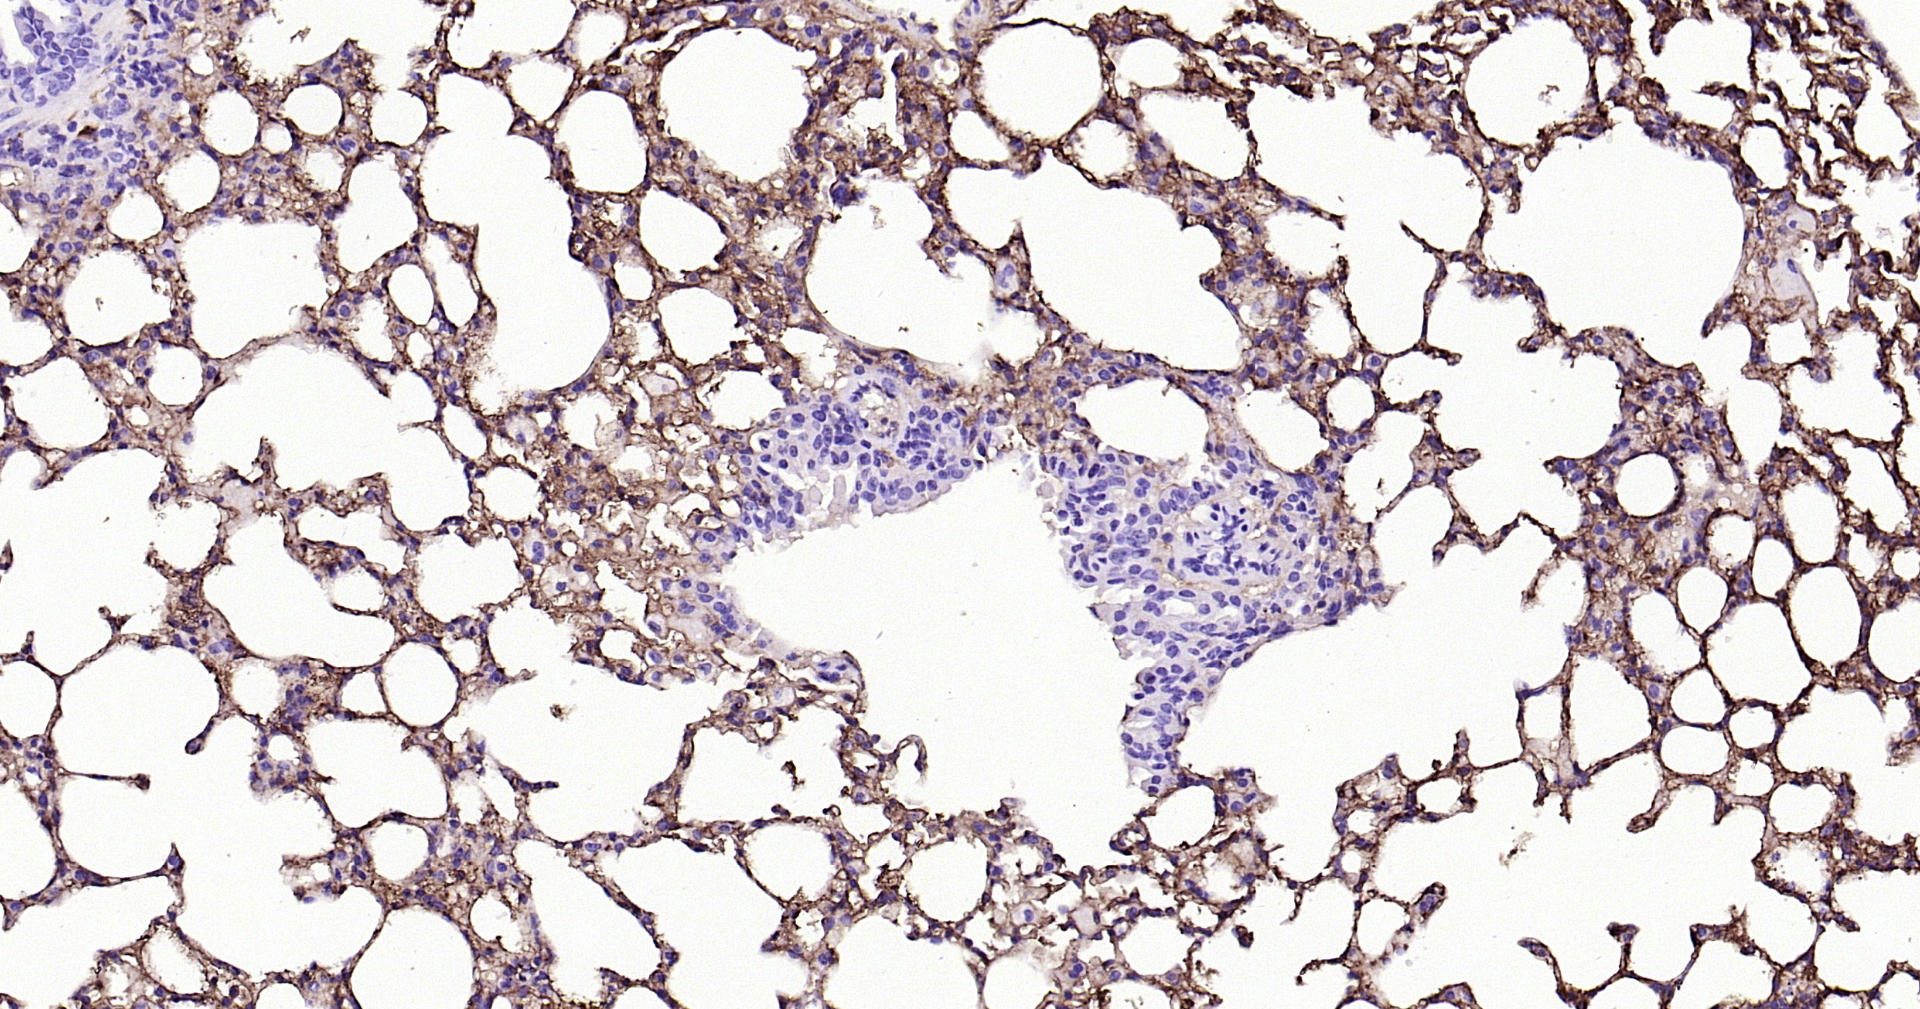

Applications IHC-P, IHC-F, IF(IHC-P)

IHC-P 1:200-1000